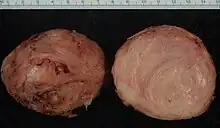

Fibroids are a type of uterine leiomyoma. Fibroids grossly appear as round, well circumscribed (but not encapsulated), solid nodules that are white or tan, and show whorled appearance on histological section. The size varies, from microscopic to lesions of considerable size. Typically lesions the size of a grapefruit or bigger are felt by the patient herself through the abdominal wall.[1]

Microscopically, tumor cells resemble normal cells (elongated, spindle-shaped, with a cigar-shaped nucleus) and form bundles with different directions (whorled). These cells are uniform in size and shape, with scarce mitoses. There are three benign variants: bizarre (atypical); cellular; and mitotically active.

Multiple uterine leiomyoma

Multiple uterine leiomyoma Large subserosal fibroid

Large subserosal fibroid Multiple uterine leiomyoma with calcification

Multiple uterine leiomyoma with calcification